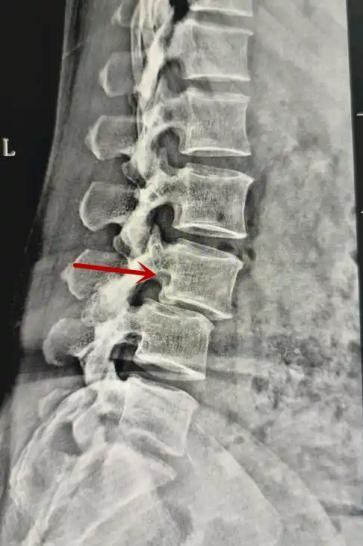

利器一:X線/DR

腰椎X線片作為最基礎的影像檢查手段,利于X線穿透人體組織后成像,以其快捷、直觀、價格低廉的特點,X線檢查主要包括腰椎正側位、雙斜位以及過伸過屈位。主要用于觀察腰椎骨骼的情況,如椎體是否有骨折、骨質增生程度、生理曲度的變化、椎體移位的情況等。然而,X線檢查也有它的局限性,無法判斷是骨折的新舊,對于椎體內部結構和周圍肌肉韌帶組織(如脊髓神經、椎間盤、韌帶等)的顯示不佳,另外X線作為有輻射檢查,孕婦及嬰幼兒謹慎選擇。

箭頭提示腰1椎骨折

箭頭提示腰3椎體滑脫